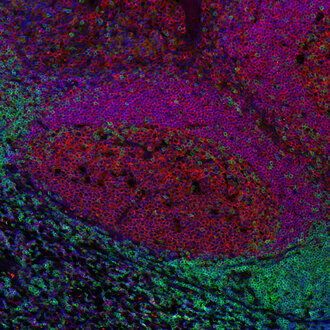

Immunofluorescence image of a human FFPE tonsil section stained for CD19 (B cells, red) and CD3e (T cells, green)